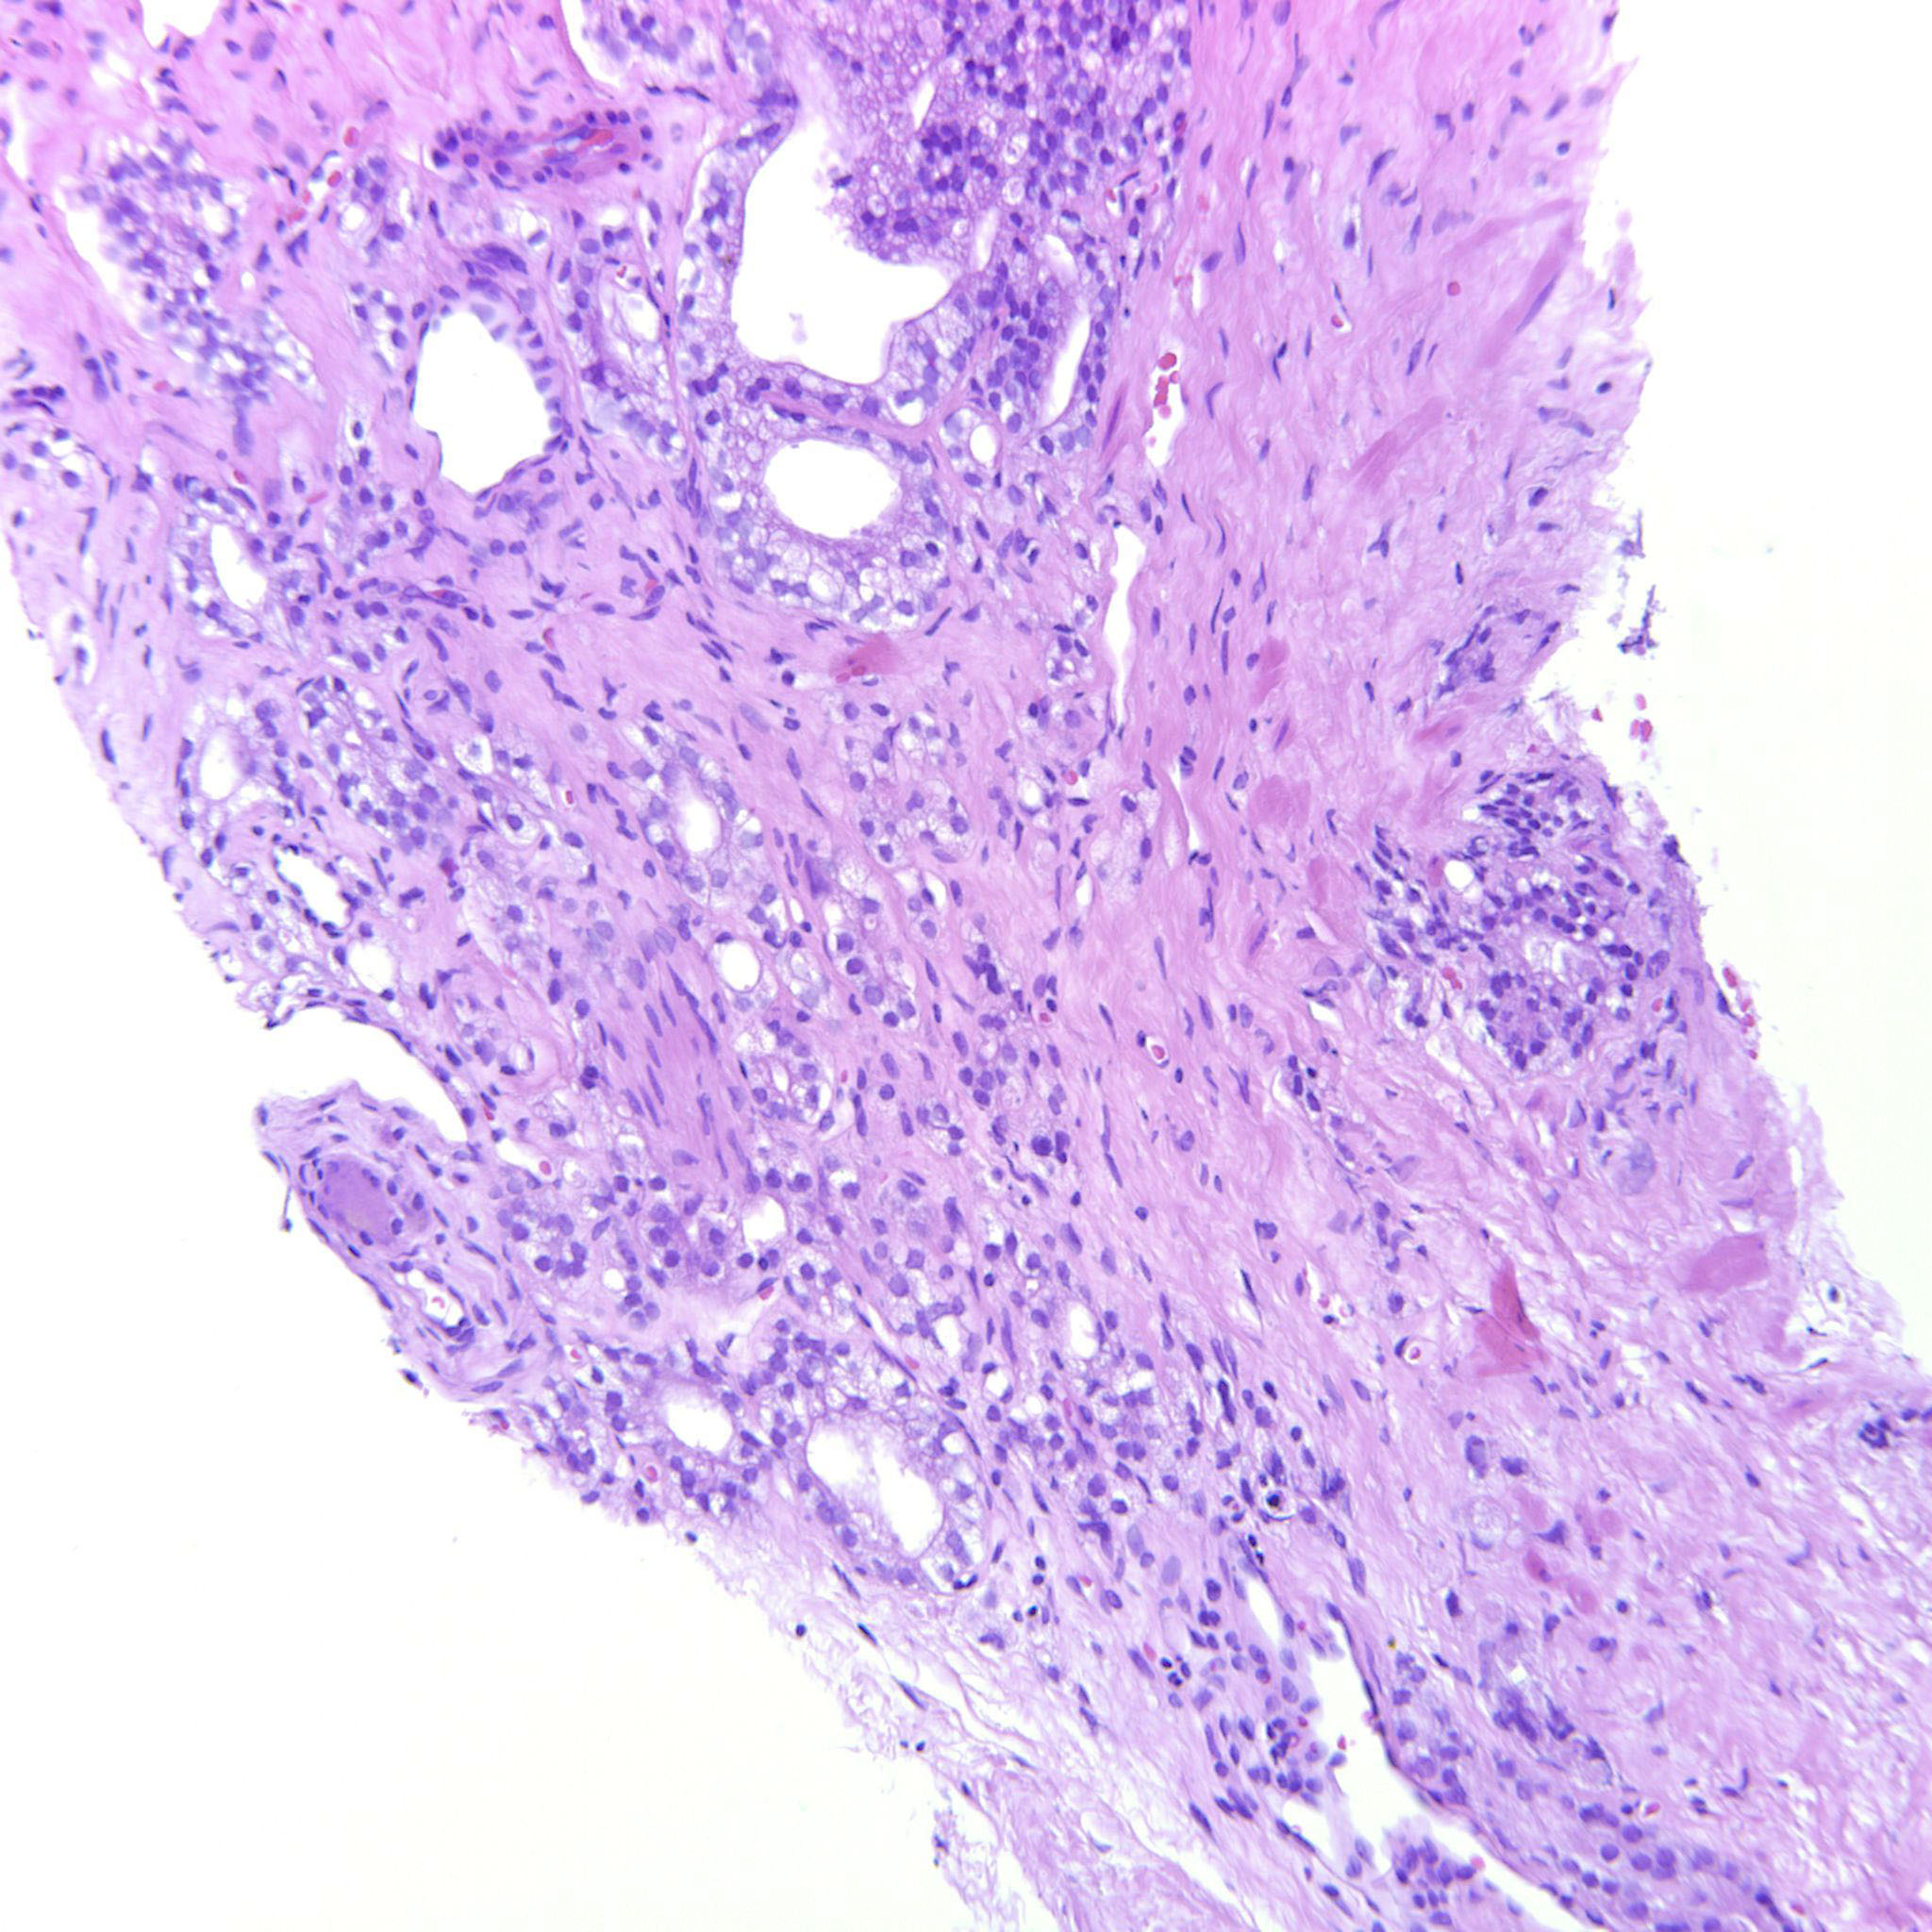

Prostate cancer grading

Case ID: 635